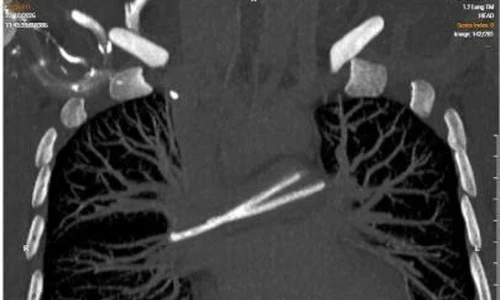

TPO - Giải chạy “Hành trình tiếp sức” 2025 vừa được Bệnh viện K khởi động, mang theo thông điệp sẻ chia và niềm tin cho cộng đồng, thu hút hàng ngàn vận động viên tham gia. Trong đó nổi bật là hành trình đặc biệt của một người đàn ông mang trong mình căn bệnh ung thư phổi nhưng đã trở thành chiến binh thực thụ trên đường chạy - minh chứng sống động cho sức mạnh niềm tin và khát vọng sống, khát vọng cống hiến.